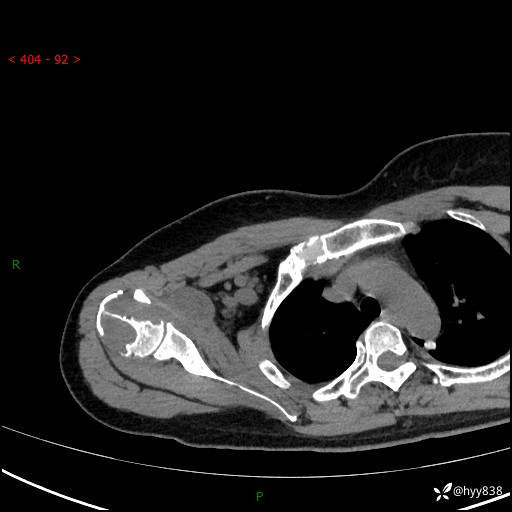

右肩关节平片

右肩关节CT平扫